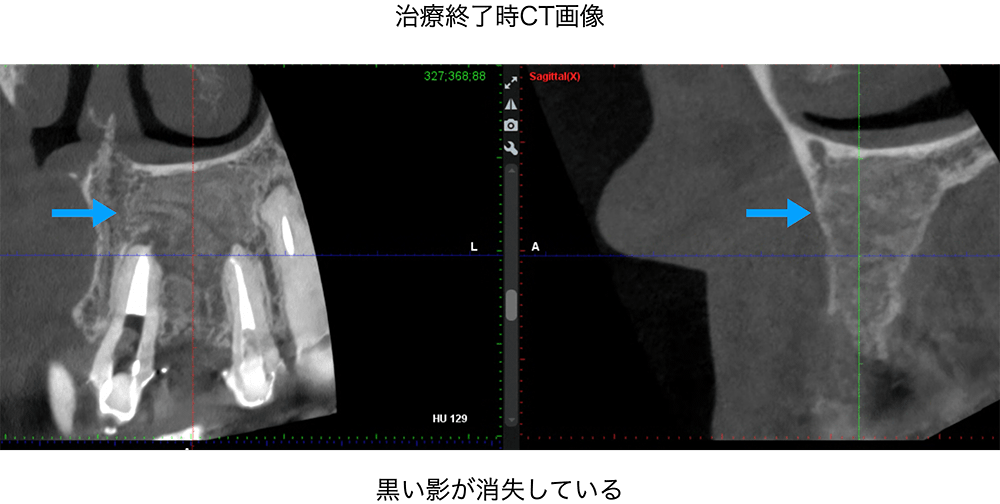

金山デンタルクリニックでは、治療の前に必ずCT撮影を行い、神経の本数や根の形、病変の大きさを正確に診査。治療の可能性や成功率まで含め、CTの画像を見せながら丁寧にご説明しています。治療後の経過もマイクロスコープやCT画像をお見せしながら、ご説明させていただきます。

金山デンタルクリニックでは、再治療が難しい症例や、根の先に大きな病変がある症例に対し、歯根端切除術などの外科的処置も行っています。

学会ガイドラインに基づく外科的歯内療法では、80〜90%の成功率が報告されており(※AAEガイドライン等)、正しい手順を踏めば、まだ歯を残せる可能性は十分にあります。